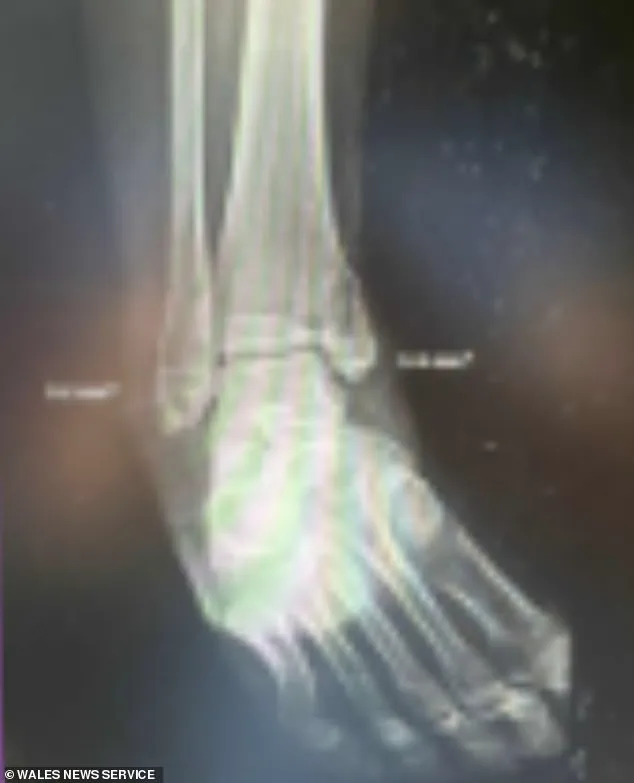

On July 4, the young woman plummeted 30ft during a hike with children, sustaining a fractured spine, two shattered feet, and internal bleeding.

Her fall resulted in spinal and foot fractures requiring multiple surgeries, internal bleeding, and admission to the intensive care unit.’ The family added that Charlotte’s recovery requires specialist care via the NHS and the emotional support of loved ones, which they are unable to provide while she remains in the US.